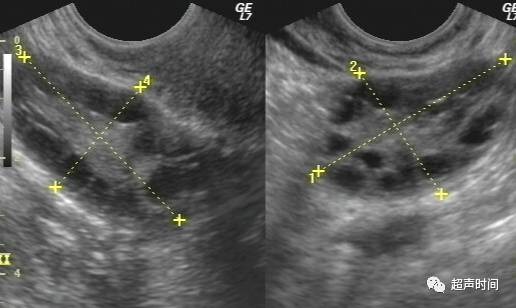

7卵巢多囊性改变

临床诊断多囊卵巢,超声所见:左侧卵巢大小约 48 x 40 x 24 mm,右侧卵巢大小约 45 x 36 x 26 mm,髓质回声增强,一个切面不少于 10 个卵泡,最大直径 4 mm。

图 13 卵巢多囊性改变,髓质回声增强,皮质内见多个小卵泡